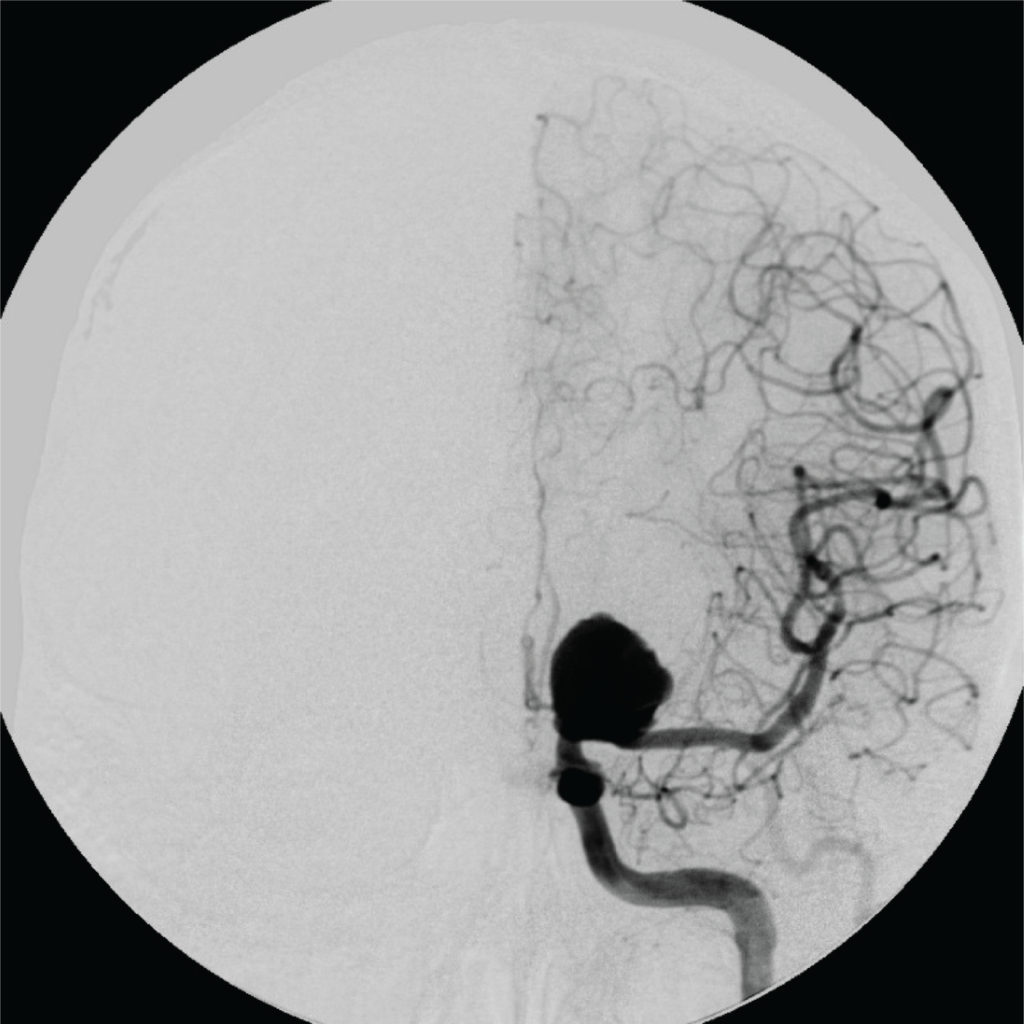

- 3. Angiografia Cerebral (ou arteriografia)

Em situações específicas, pode ser indicado um exame mais detalhado, chamado angiografia cerebral.

Esse exame é mais invasivo e costuma ser reservado para casos em que é preciso avaliar melhor o aneurisma ou planejar um tratamento.

Depois que o aneurisma é identificado, o médico avalia os exames para decidir se o aneurisma pode apenas ser acompanhado com consultas e exames regulares ou se precisa de algum tipo de tratamento.